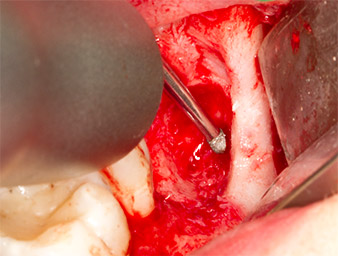

Um den Wurzelrest gewebeschonend frei zu präparieren, kam ein weiteres Instrument zum Einsatz (Piezomed S2), das primär für die Präparation des lateralen Fensters bei Sinusboden-Augmentationen indiziert ist. Zusätzlich wurden mit der diamantierten Kugel scharfe Knochenkanten geglättet (Abb. 6 und 7). Alle eingesetzten Piezomed-Aufsätze arbeiteten mit der jeweiligen automatischen Standardeinstellung ohne Booster-Funktion.

Piezomed S2

Abb. 6: Mit einem diamantierten kugelförmigen Instrument (Piezomed S2) wird der Wurzelrest vorsichtig frei präpariert, Knochenkanten werden geglättet.

Wurzelrest 38

Abb. 7: Der Wurzelrest 38 ist in seiner Alveole gut dargestellt für die nachfolgende Entfernung.